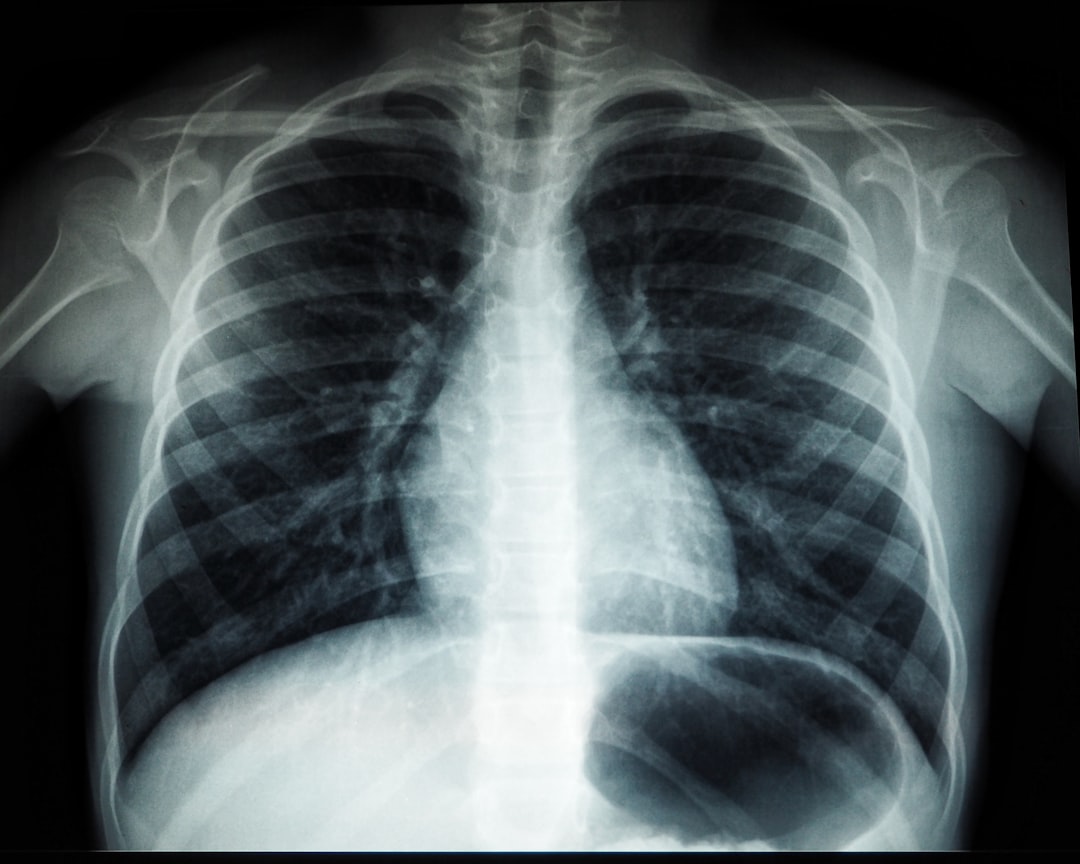

검사 과정은 매우 간단합니다. 결핵 검사는 주로 피검사(잠복 결핵 검사)와 흉부 X-ray 촬영으로 이루어져 있습니다. 처음 검사에 대한 불안감을 느낀다면, 제가 겪었던 경험을 공유하겠습니다. 검사 받기 전 조금 긴장했지만, 일단 시작하니 생각보다 쉽게 마칠 수 있었습니다!

피검사는 보통 손가락에 바늘을 찔러 혈액을 채취하고, 이 피를 통해 결핵 감염 여부를 확인합니다. 그리고 흉부 X-ray 촬영은 방사선 촬영을 통해 폐의 상태를 확인하는 과정입니다. 이 두 검사는 전반적인 결핵 검사 과정에서 필수적인 단계에 해당합니다.